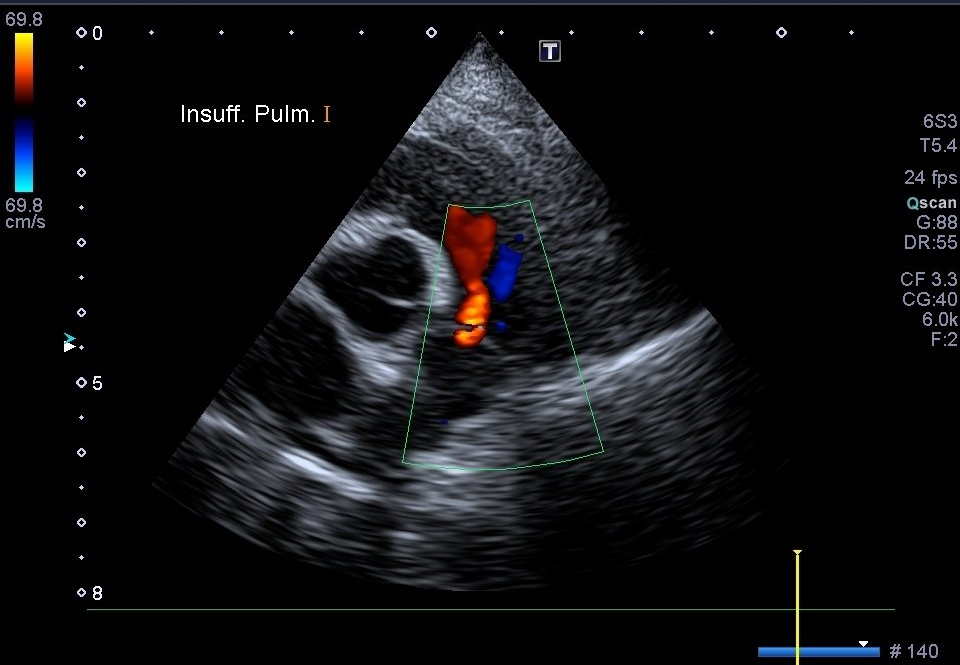

Échographie Cardiaque

L’échocardiographie est utilisée comme son nom l'indique dans l’exploration spécifique du coeur. Elle permet donc particulièrement le suivi des maladies cardiaques.

Nous pouvons mesurer précisément les cavités du coeur, observer la contraction du muscle cardiaque et ainsi visualiser la circulation du sang. Elle peut être complétée par une mesure de la tension artérielle et la réalisation d’un électrocardiogramme, conjointement à d’autres examens comme la radiographie thoracique.